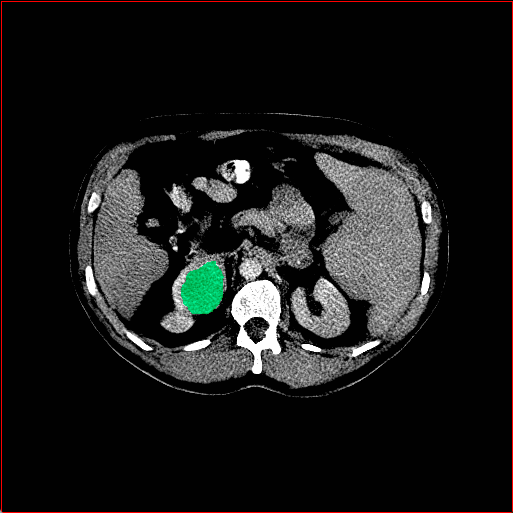

Liver Tumor

0.75×0.75×0.50.75\times 0.75\times 0.5

mm

512×512×768512\times 512\times 768

Figure 4: MAISI-v2 segmentation-guided results for five types of tumors. We show results for different voxel spacing and volume size to demonstrate the flexibility of MAISI-v2. Different Hounsfield Unit window is used to better show the contrast between tumor and normal tissues.